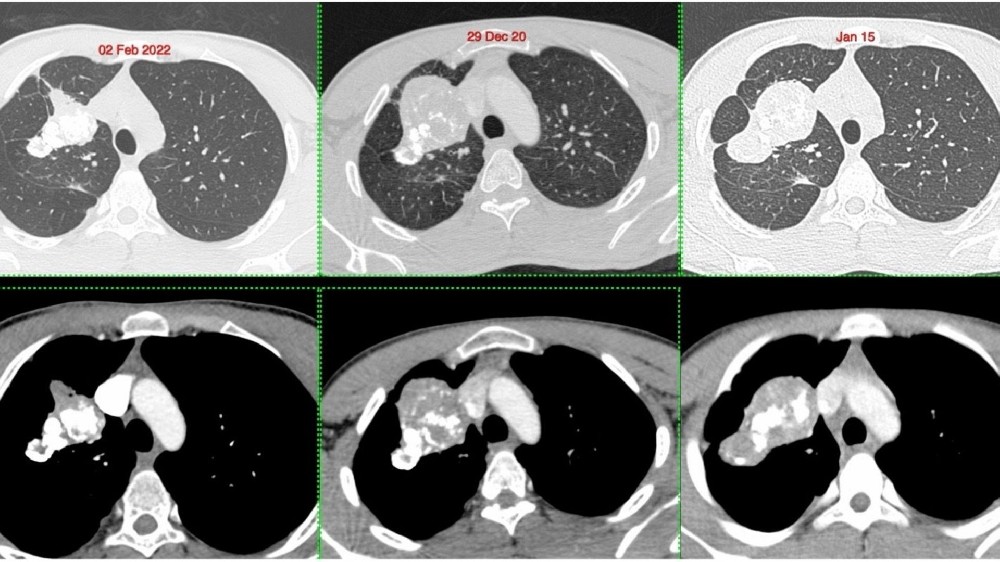

肺部發炎性肌纖維母細胞腫瘤的分期與存活率

準確的分期對肺發炎性肌纖維母細胞腫瘤患者的臨床管理和預後有重大影響。分期評估腫瘤的大小、位置、轉移擴散和全身受累情況。香港和亞洲地區的研究顯示,基於可用的醫療基礎設施和診斷能力,患者的表現、治療方法和存活率均有所不同。